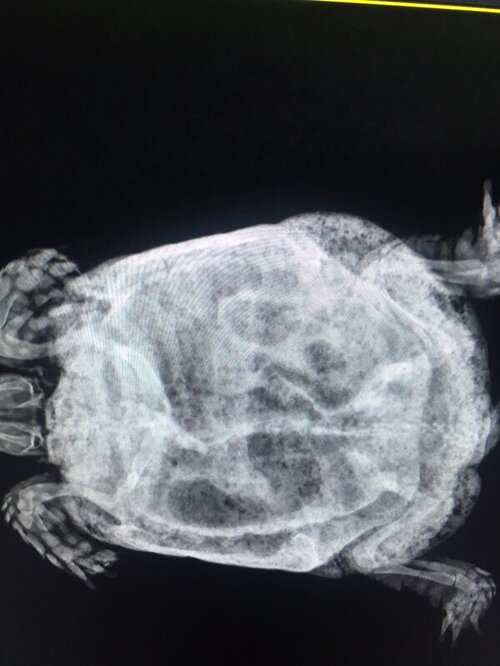

по такой проекции невозможно определить есть у черепахи пневмония или нет. На ней видно только жкт.

Черепаха внешне в очень плохом состоянии. Учитывая условия содержания и возраст тут с большей вероятностью уже проблемы с почками. Пневмония тоже может быть бонусом из-за имуносупрессии.